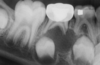

periapical cyst

periapical cyst

periapical cyst

radioluscency extends from mandibular frist molare to the contralateral first molar

periapical cyst